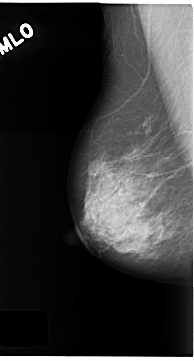

C_0180_1.LEFT_MLO

LEFT_MLO LINES 4720 PIXELS_PER_LINE 2512 BITS_PER_PIXEL 12 RESOLUTION 50 OVERLAY